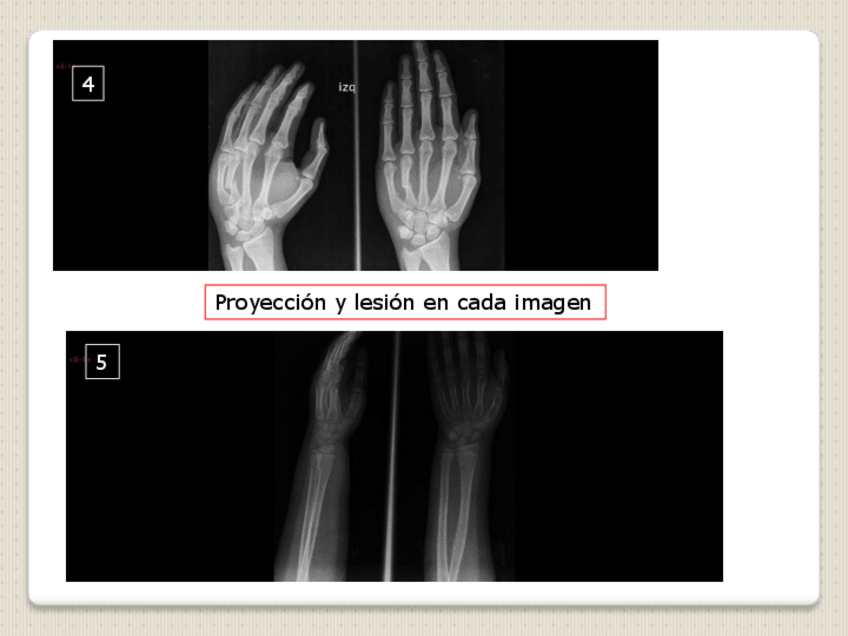

He publicado nuevos examenes de 2º Radiología en Fisioterapia: Examen-MMSS.pdf

He publicado nuevos examenes de 2º Radiología en Fisioterapia: MODELO-4-examen-EJERCICIO-PRACTICO-copia.pdf

He publicado nuevos examenes de 2º Radiología en Fisioterapia: MINIEXAMEN-MODELO-EJERCICIO-PRACTICO-copia.pdf